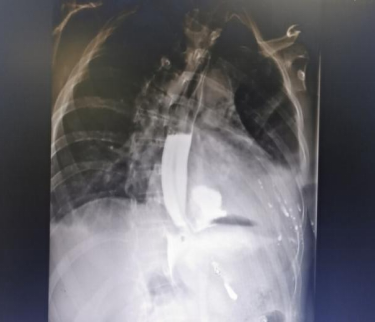

比如这位朋友 , 喝酒后呕吐不止 , 还出现肚子痛、背痛 , 送到医院来高度怀疑是食管破裂 , 检查出来一看 , 果真食管下段破裂了一个0.8cm宽的口口 。